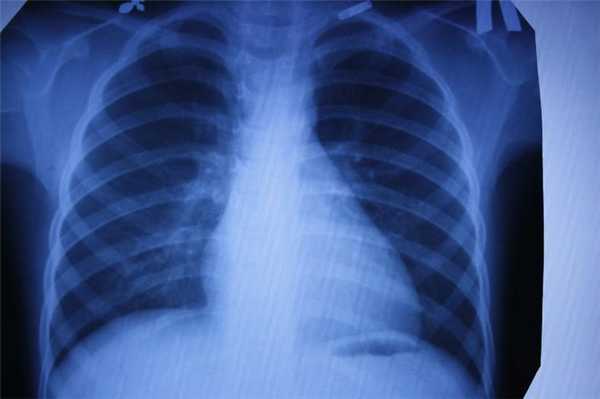

Каждый метод дает разную информацию об исследуемых органах. Если говорить в целом, то КТ идеально «видит» легкие, и превосходит все другие методы в выявлении патологии дыхательной системы: и МРТ и рентген и флюорографию.

Для выявления патологии легких также назначают рентген и флюорографию…

Если речь идет о профилактическом осмотре, ежегодной диспансеризации, и у человека нет никаких жалоб - классическое рентгеновское исследование, которое дает меньшую, чем КТ лучевую нагрузку, можно считать достаточным. Но если пациент находится в группе риска по развитию рака легких (например, это курильщик с серьёзным стажем), лучше сразу сделать более информативную КТ. Андрей Дмитриевич Каприн, главный онколог России, рассказывает, что благодаря огромному количеству КТ- исследований легких, которые были сделаны за время пандемии, удавалось выявлять рак легких на самых ранних стадиях и множество других, не связанных с COVID-19 патологий. Низкодозовая КТ - лучший метод скрининга рака легких, она позволяет увидеть зарождающийся опухолевый процесс размером 2-3 мм и самые минимальные изменения, которые рентген может и пропустить.

С помощью компьютерной томографии в медицинских центрах СПб проводят скрининг рака легких у курильщиков. Такая томография позволяет выявить в 2 раза больше опухолей на ранней стадии. Простая флюорография (на базе рентгена) рак легких не показывает, поскольку плоскостное изображение не видит маленькие очаги опухоли, а вот на КТ можно визуализировать новообразование до 1 мм величиной.

КТ делается быстро, с его помощью проводить скрининг на рак лёгких. Также можно использовать компьютерную томографию непосредственно во время проведения хирургических операций.